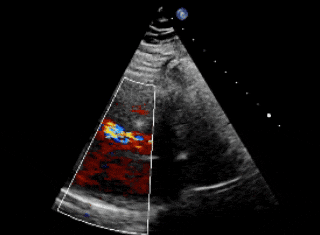

术前造影

主动脉瓣上造影,破口约5mm

释放前瓣上造影

分流明显减少